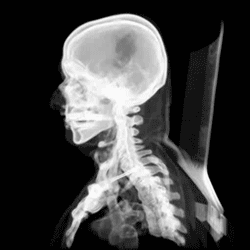

Skull of a new-born child from the side

At birth, the human skull is made up of 44 separate bony elements. During development, many of these bony elements gradually fuse together into solid bone (for example, the frontal bone). The bones of the roof of the skull are initially separated by regions of dense connective tissue called fontanelles. There are six fontanelles: one anterior (or frontal), one posterior (or occipital), two sphenoid (or anterolateral), and two mastoid (or posterolateral). At birth, these regions are fibrous and moveable, necessary for birth and later growth. This growth can put a large amount of tension on the "obstetrical hinge", which is where the squamous and lateral parts of the occipital bone meet. A possible complication of this tension is rupture of the great cerebral vein. As growth and ossification progress, the connective tissue of the fontanelles is invaded and replaced by bone creating sutures. The five sutures are the two squamous sutures, one coronal, one lambdoid, and one sagittal suture. The posterior fontanelle usually closes by eight weeks, but the anterior fontanel can remain open up to eighteen months. The anterior fontanelle is located at the junction of the frontal and parietal bones; it is a "soft spot" on a baby's forehead. Careful observation will show that you can count a baby's heart rate by observing the pulse pulsing softly through the anterior fontanelle.

The skull in the neonate is large in proportion to other parts of the body. The facial skeleton is one seventh of the size of the calvaria. (In the adult it is half the size). The base of the skull is short and narrow, though the inner ear is almost adult size.[15]